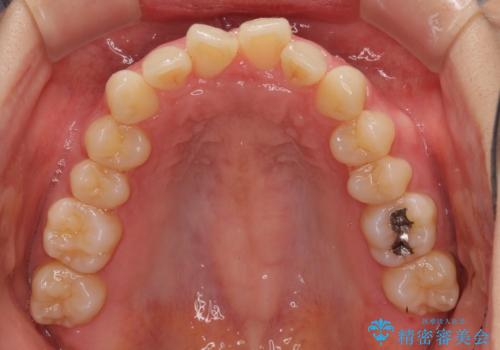

インビザラインによるディープバイトの改善

- 口元の前突感と深い咬み合わせ(ディープバイト)を気にして来院された患者様です。

インビザラインによる上下歯列の遠心移動(後方移動)と、それに伴う近心傾斜(前方傾斜)の改善により、口元の突出感とディープバイトを改善することとしました。

前歯のデコボコを最も気にしていましたが、咬み合わせが深く歯ぎしりが自由にできない点を指摘すると、常に食いしばってしまうことも悩みであることが分かりました。

咬合状態が大きく変化したため、治療後半では咬み合わせの位置が定まらなくなりました。上下の前歯に後戻り防止用のワイヤーを装着し、奥歯の咬合をフリーにしたことで1ヶ月ほどで咬み合わせが定まりました。